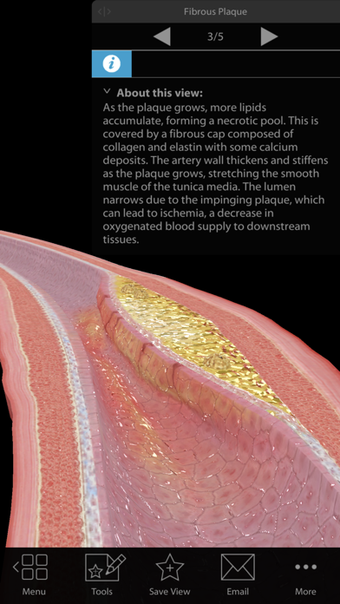

Argosy Publishing による iPhone 用の完全版アプリ。

Physiology Pathologyは iPhone 用のフル バージョンのソフトウェアで、 「医学」カテゴリの一部です。

iPhone用の生理学病理学について

生理学 病理学は、iOS 12.1.2 以降で利用できます。アプリの現在のバージョンは 1.1.39 で、英語、ドイツ語、イタリア語で実行できます。